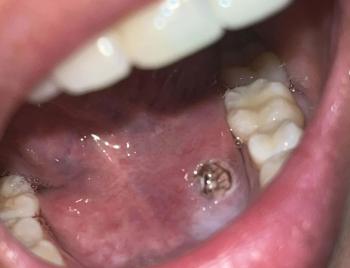

1. Visual Findings (Deep Image Review)

Upper and lower anterior teeth (front teeth):

Visible dark discoloration and plaque accumulation along the gumline.

Signs consistent with early childhood caries (ECC), commonly affecting front teeth first.

Enamel condition:

Areas of enamel demineralization (chalky or dull appearance).

Possible early cavitation on at least one anterior tooth.

Gingival tissues:

Mild inflammation suggesting plaque-induced gingivitis.

Dentition stage:

Appears to be primary or mixed dentition, which is more vulnerable to rapid decay.

2. Most Likely Diagnosis

Early childhood caries (anterior teeth)

Enamel demineralization

Plaque-induced gingivitis

High caries-risk pediatric profile